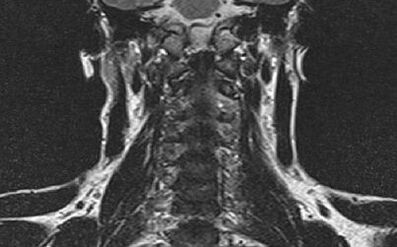

In addition to an X -ray for the patient, the doctor prescribes computerized tomography and (or) magnetic resonance imaging. These studies are necessary to establish accurate diagnosis and prescribe correct treatment.

For this, a standard examination standard has been adopted, which includes a general biochemical blood test, radiographic examination, magnetic resonance imaging and ultrasound.

For a reliable determination of Gonartrosis and the stadium of its development, a further examination is used in combination with X -Ray: on ultrasound devices, magnetic resonance imaging or coach.